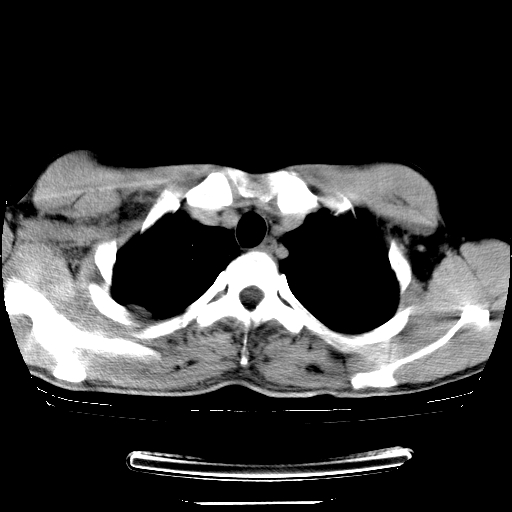

以下是引用dyqct在2008-4-29 8:43:00的发言:[br][br] 支持右侧胸腔包裹性积血。闭式引流管是不是插的太深了?

以下是引用zjzjr在2008-4-29 14:11:00的发言:[br]支持右侧胸腔包裹性积血。闭式引流管是不是插的太深了?胸腔引流,引流管快进入纵隔了.